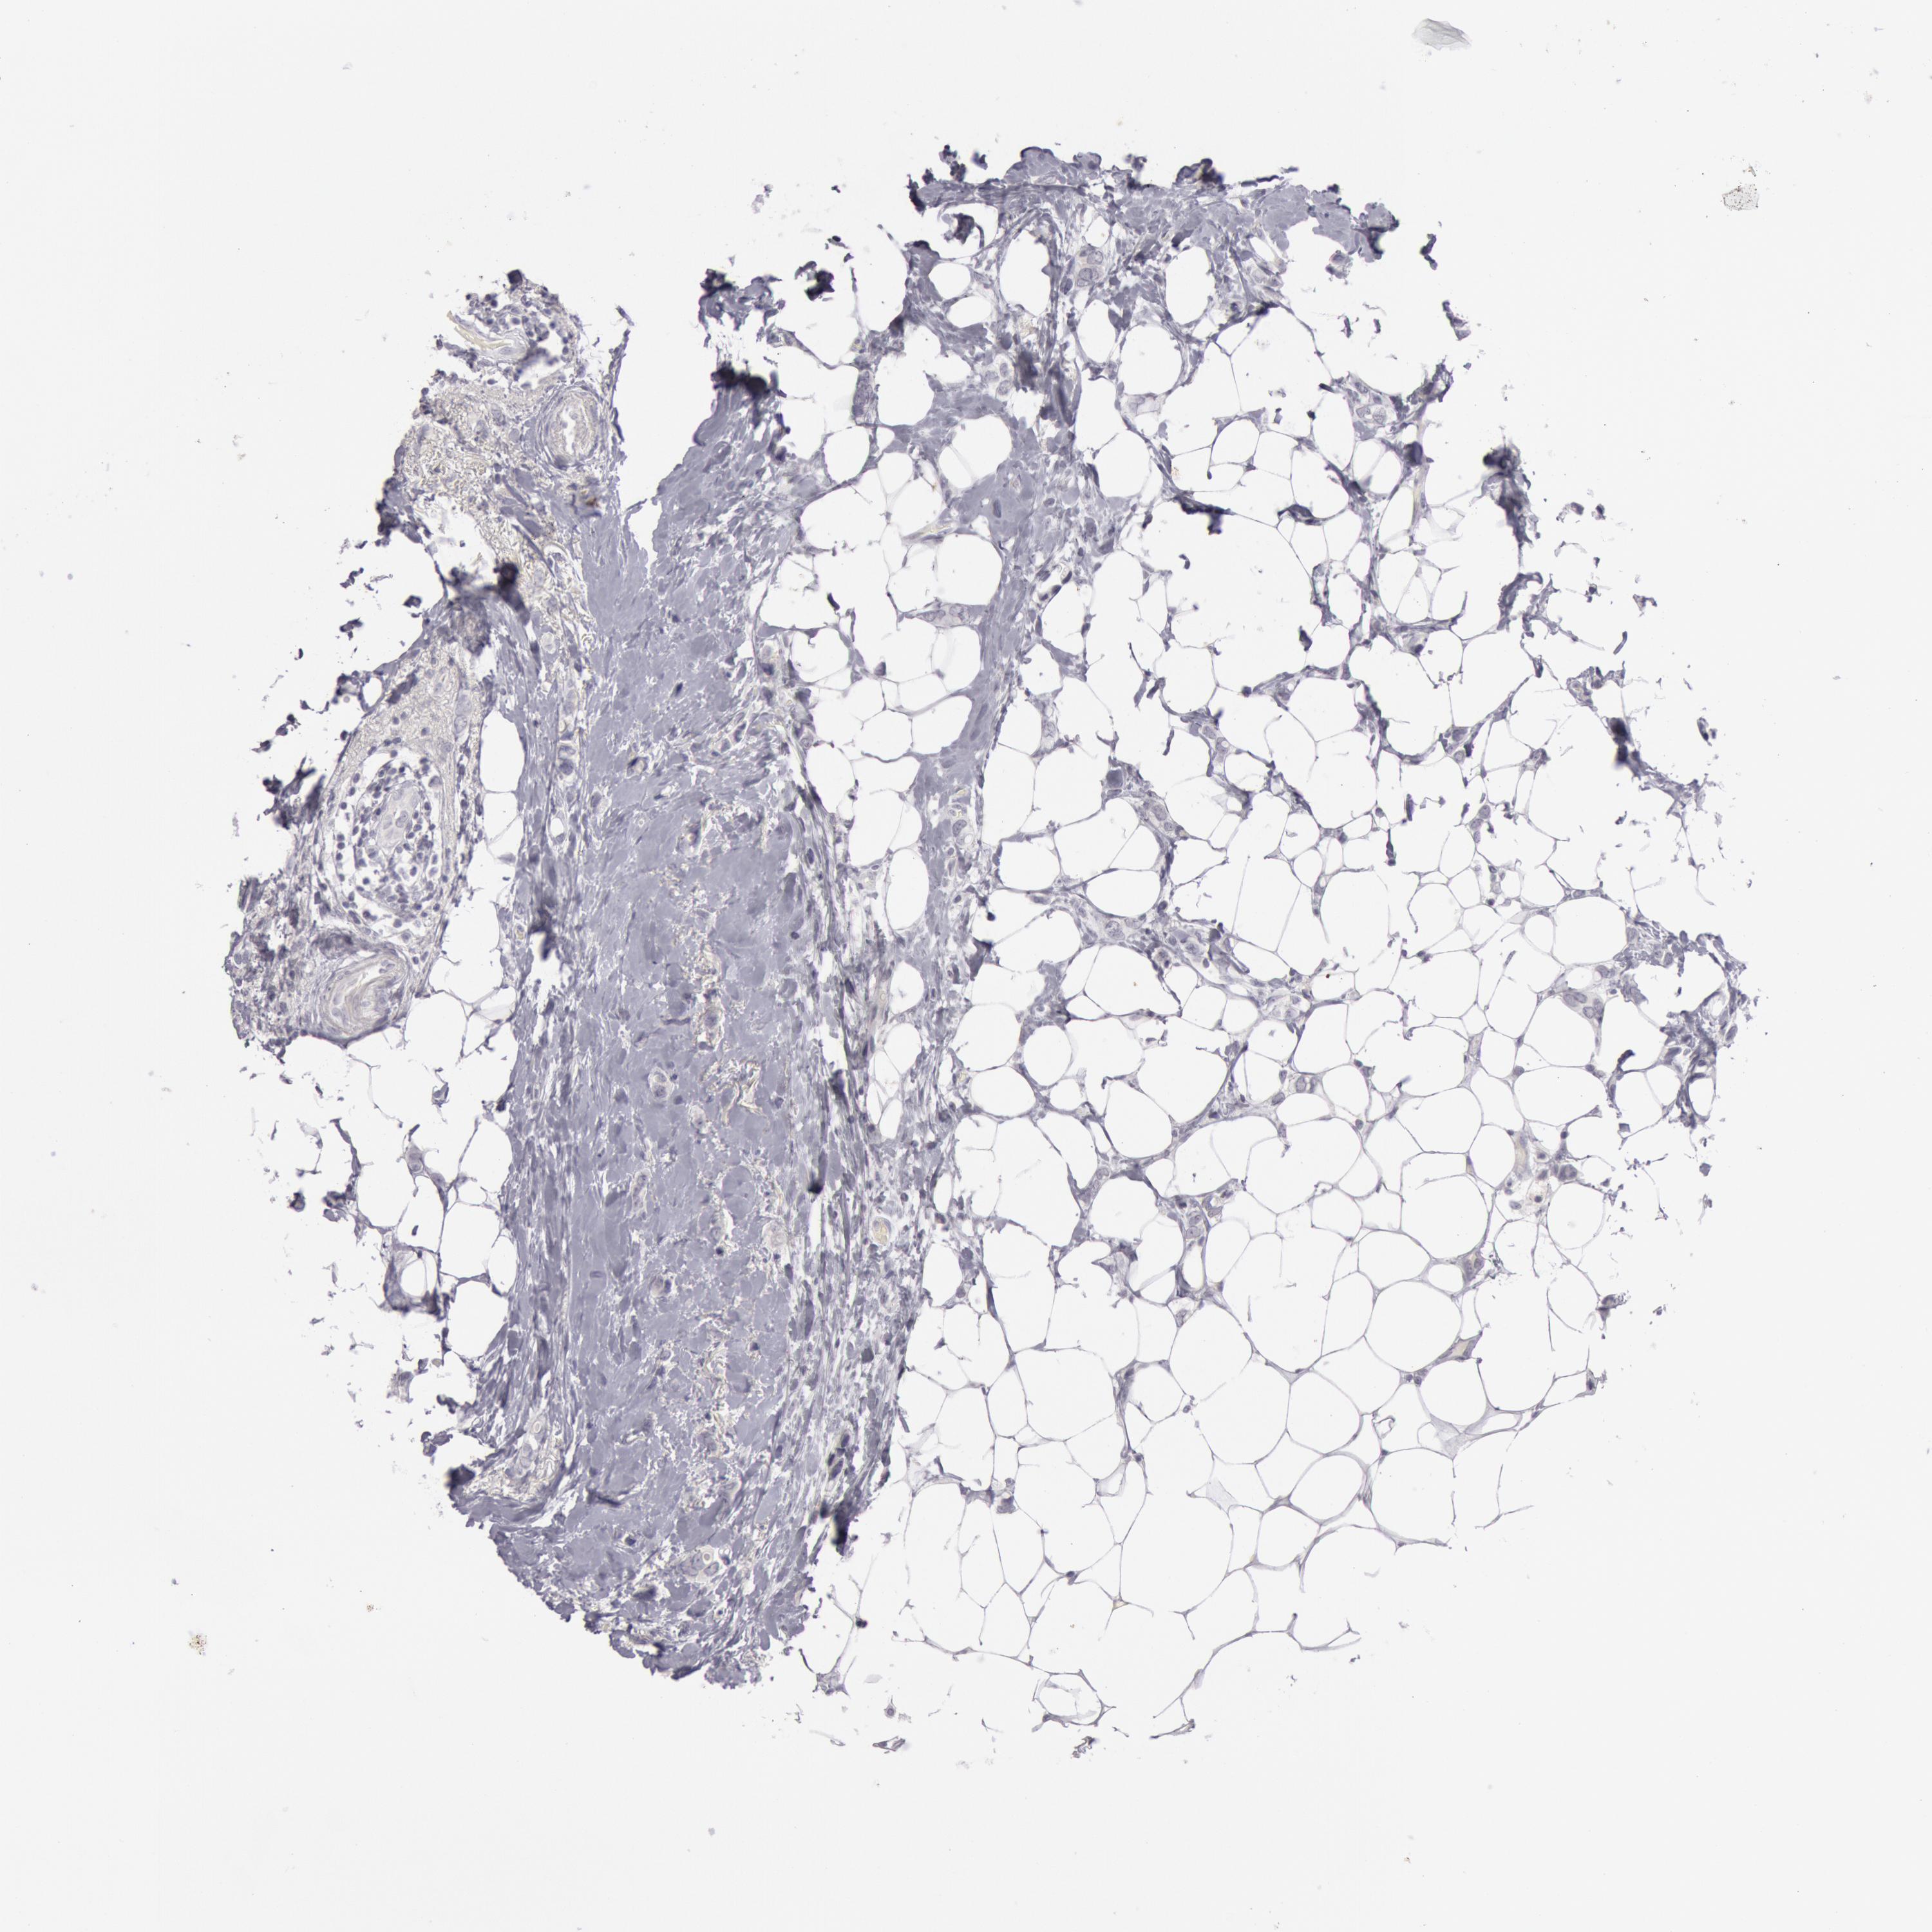

BRCA TCGA BRCA VALIDATION PROTEIN EXPRESSION